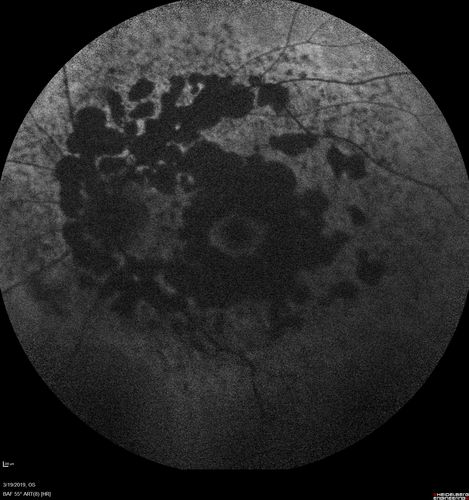

Concentric Geographic Atrophy - 76 year old man

Gradual vision loss, worse at night. VA 20/40 OU.

Concentric Geographic Atrophy - 76 YO male